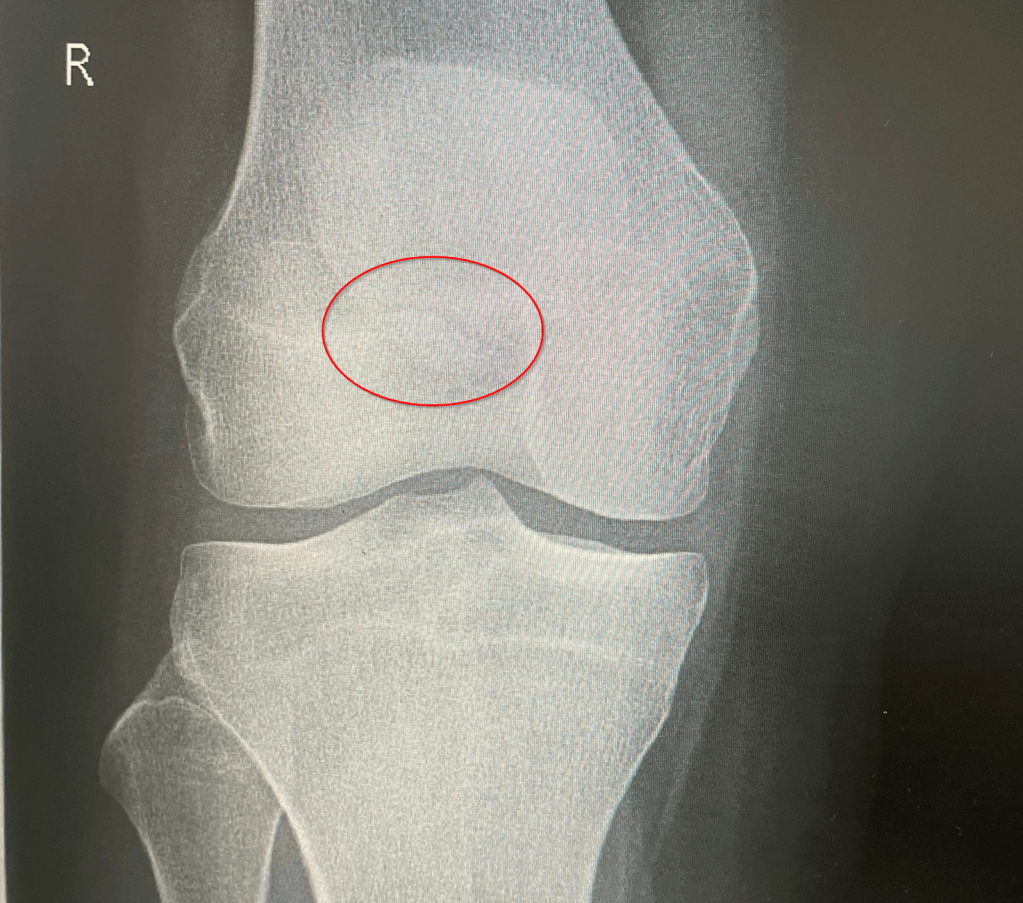

Diese Woche Freitag steht der heiß ersehnte Termin beim Orthopäden an. Das (hoffentlich) letzte Mal röntgen. Wenn ich dort das Okay bekomme, kann es endlich wieder mit dem Laufen und dem Muskelaufbau des rechten Beins los gehen. Momentan ist der Oberschenkelmuskel noch immer eher ein schwabbeliges Etwas und ich freue mich schon darauf, diesen in das zu verwandeln, was er einmal war. Ich bin sehr gespannt, wie der Einstieg ins Laufen klappen wird und wie schnell ich meine Ausdauer wiederaufbauen kann. Ihr werdet es hier auf jeden Fall erfahren!